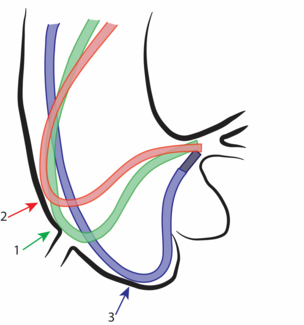

A 76-year-old man diagnosed with severe pure native aortic regurgitation underwent transcatheter aortic valve replacement due to high surgical risk. The computed tomography angiography showed no calcification and no stenosis of the aortic...